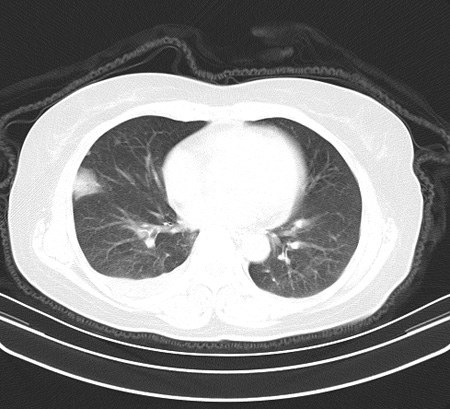

以下是引用余辉在2009-2-19 20:10:00的发言:[br]多考虑急性感染性病变,右中叶尚可见多枚小斑片状影,多为化脓性肺炎,双侧胸腔积液

以下是引用随光逐影在2009-2-19 20:33:00的发言:[br]1)考虑右肺炎症;建议抗炎治疗后复查。2)双侧胸腔积液(以右侧为甚)。

以下是引用花凤凰在2009-2-19 20:46:00的发言:[br]病人有发热,胸痛急性起病,主要病变位于右肺中叶外侧段,呈楔行改变,位于外带胸膜下,考虑为肺梗塞可能!!!!!!!!!!!!!!!!!!!!!!!!!!!!!!!!!!!